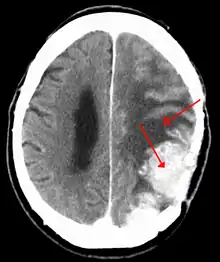

| A contrast-enhanced CT scan of the brain, demonstrating the appearance of a meningioma | |

Meningiomata are visualized readily with contrast CT, MRI with gadolinium,[18] and arteriography, all attributed to the fact that meningiomata are extra-axial and vascularized. CSF protein levels are usually found to be elevated when lumbar puncture is used to obtain spinal fluid. On T1-weighted contrast-enhanced MRI, they may show a typical dural tail sign absent in some rare forms of meningiomas.[15]